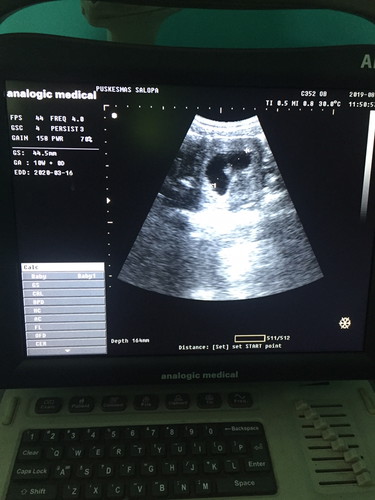

Usia 10week tp dedenya kok segitu ?? Panjangnya sih 4.45cm tp kok kecil bgt ya bun? Bidan bilang gkpp normal aja kok, adakah yg sama bunda disini ??

Baca lagiBunda cba usg di tempat lain karna itu seperti nya yg di ukur kantong hamil nya bukan janin nya... Saya 10wekk kmaren udah nampak bentuk janin bun ... Klw yg saya lihat dr usg nya bunda masih kayak embrio... Cba ke spog aja.. siapa tau klw ada keterlambatan pertumbuhan bisa di kasih vitamin ...

Normal bund , bubid kan uda blg normal kan ya ? Janin 10week emng masih kecil . Nti deh 16week usg lagi udh keliatan gede . Alhamdulillah 10week udah keliatan janinnya , banyak yg usia segitu blum keliatan , dsuruh balik lagi 1-2mnggu